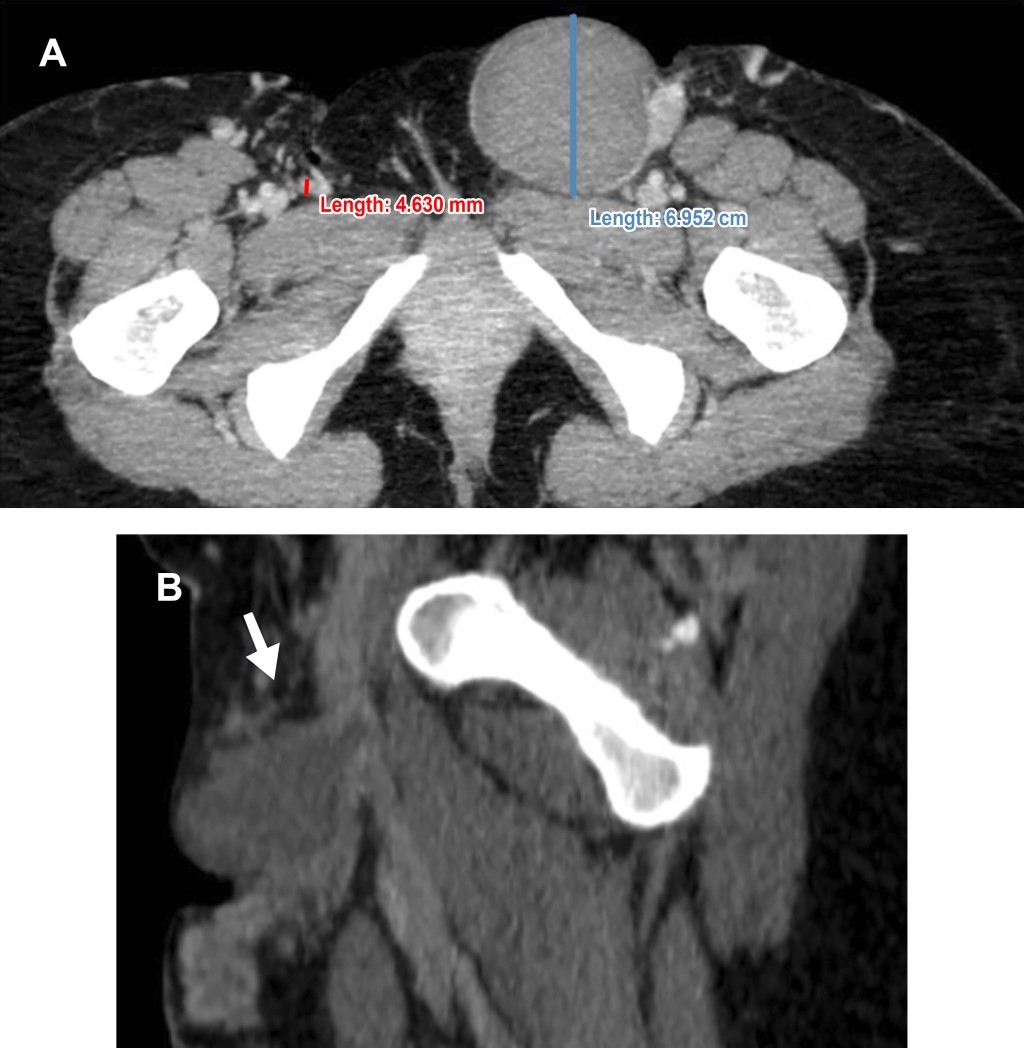

A la inspección se observan trayectos varicosos trombosados en segmento correspondiente de safena accesoria anterior. Angiotomografía con hallazgo de aneurisma venoso de 6.9 cm diámetro mayor, dependiente de safena mayor en su Union Safeno Femoral (USF), con relación a 4 mm de safena mayor contralateral (Figura 1).

Figura 1